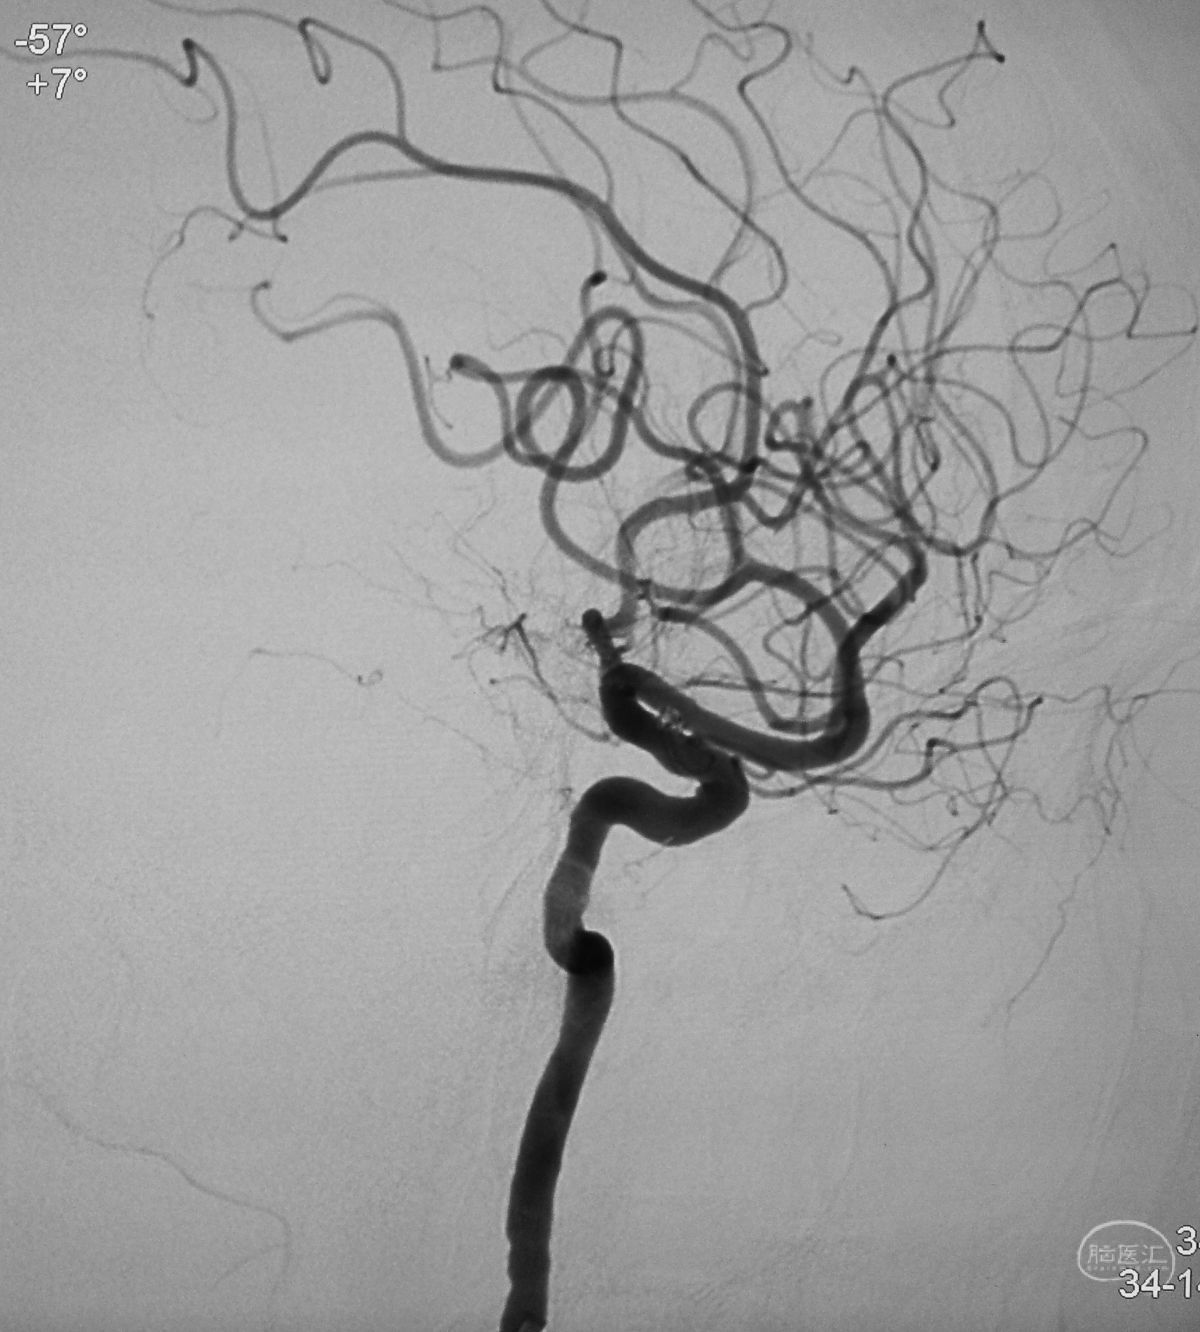

病例一,左侧微小眼动脉瘤,未破裂。

测量:瘤体2.09×2.34 mm,颈宽2.66 mm。

工作位造影

Traxcess 14微导丝可以进入瘤腔,但头端塑成S形的Echelon 10微导管无法跟入。

将微导管在虹吸弯处成襻,越过瘤颈,管头折返钩入瘤腔,即所谓回马枪技术。